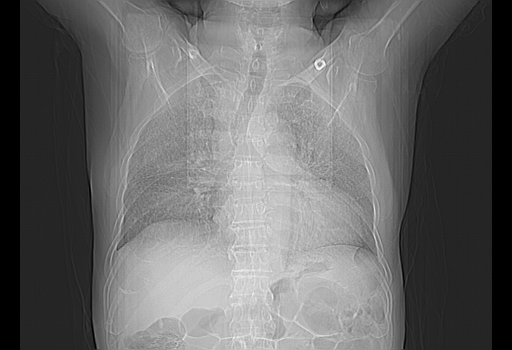

今天复查肺部CT,发现双肺广泛磨玻璃样改变。所以我把3月19日和5月9日相隔50天的肺部CT上传。请大家会诊。

5月9日肺部CT(在4月27日齐鲁医院肺部CT描述部分肺组织磨玻璃样改变,12天后肺组织广泛磨玻璃样改变)

2009年5月9日肺部CT

大致读了系列胸部CT:纵隔窗无明显异常,肺窗:从4、27至今:主要是双肺中下野外带可见毛玻璃样改变,目前处于急性肺泡炎阶段,至于原因考虑1、结替组织或胶原血管性疾病所致?2、恶性疾病如恶组在肺部所致的表现或细支气管肺泡癌?3、药物或其它原因如肺蛋白沉着症所致肺泡炎目前不太可能?总之,明天就去请我院的呼吸科、感染科、血液科和临免专家会诊哈。